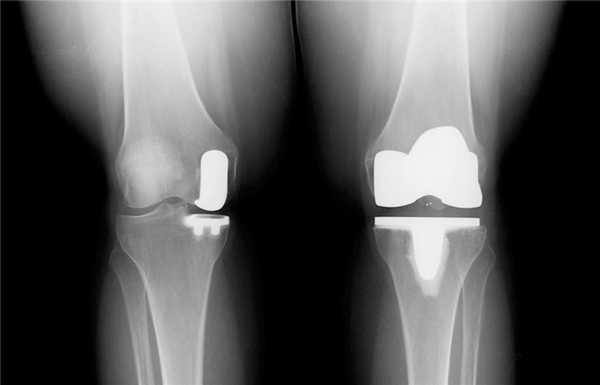

Сравнение двух типов операций.

Длительное время ТЭКС (тотальное протезирование коленного сустава) признавался ведущим методом при лечении остеоартроза. Какие же преимущества имеет одномыщелковое эндопротезирование:

- Гораздо меньший объем хирургического вмешательства;

- Быстрый восстановительный период (уже через несколько месяцев пациент может возвращаться к своим повседневным физическим нагрузкам);

- Менее выражен болевой синдром (как в покое, так и при интенсивной физической нагрузке);

- После частичного эндопротезирования люди вдвое реже жалуются на трудности при использовании автомобиля, чем после тотального;

- Вдвое меньше случаев ограничения сгибания в коленном суставе и контрактур;

- Гораздо чаще людям с частичным эндопротезом доступно положение сидя на корточках, посадка и выход из автотранспорта, наклон и подъем предметов с пола, бег.

Целый ряд неоспоримых и важных преимуществ однополюсного протезирования. Большинство зарубежных коллег подчеркивают у себя схожесть приведенных результатов.